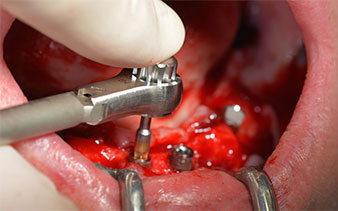

Le prochain réglage programmé est destiné à la mise en place des implants. Dans notre cabinet, nous appliquons généralement un couple de 32 Ncm pour cette phase (Fig. 12 et 13).

Une grande stabilité primaire est une exigence essentielle à la restauration immédiate. Pour s'en assurer, le forage n'a pas été taraudé ici. L'unit de chirurgie Implantmed W&H utilisé ici est doté d'un mode spécial adapté qui peut être directement sélectionné et est indispensable à de nombreuses indications. Lors du positionnement des implants, les derniers tours ont été effectués avec une valeur supérieure à 32 Ncm et ont été effectués à la clef à cliquet. Dans un tel cas, nous recommandons d'utiliser la fonction d'auto -taraudage de l'implant et de tourner plusieurs fois les implants vers l'arrière et vers l'avant.

Ceci permet à l'implant de s'approcher de la position finale progressivement sans exercer de pression excessive sur l'os (Fig. 14).